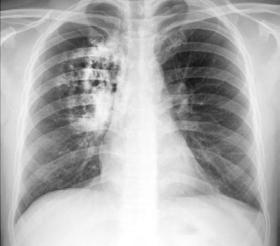

Cada año en México se diagnostican alrededor de 8,000 nuevos casos de cáncer de pulmón, lo lamentable de esta cifra, es que, en ese mismo año, mueren el 87.5% de estos pacientes por esta causa, es decir, 7,000 personas, lo que demuestra que este padecimiento es altamente mortal, señaló en entrevista con Crónica, Valentina Gallart, directora médica de AstraZeneca-México.

Resaltó que en la región de América Latina los nuevos casos diagnosticados en un año alcanzan los 320,000 personas, en tanto que a nivel mundial suman 2 millones de nuevos casos cada año.

En el país, abundó, las cifras de nuevos casos diagnosticados y fallecimientos en un año dejan ver, que, aunque, el cáncer de pulmón no es el más común, “porque existen otro tipo de cánceres que tienen mayor prevalencia, sí es el más letal a nivel mundial”.

Este índice de mortalidad

tan elevado en México, es porque el 85% de los pacientes en México y Latinoamérica son diagnosticados en etapas avanzadas, cuando el cáncer ha hecho metástasis y la probabilidad de sobrevida entre el primero y el quinto año “es menos de un 10% para estos pacientes”.

El cáncer de pulmón, aunque no es de los más frecuentes, si es altamente mortal, debido a que en la mayoría de los casos se detecta en etapas avanzadas . (Cecilia Higuera Albarrán)